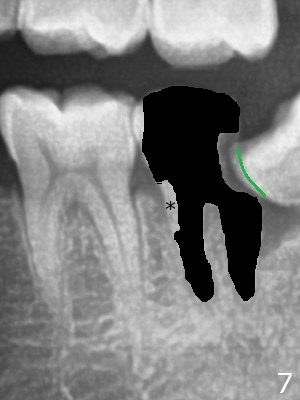

A 36-year-old man with poor dentition (smoker 1/4 ppd) requests extraction of sympto-matic teeth (#18 and 32, Fig.1). A half of Osteogen Plug is placed at #32 post extraction. To extract #18, the tooth has to be sectioned (Fig.2 red). The mesial portion is removed easy, while the distal one requires removing the mesial surface of #17 (Fig.2 green). Vanilla bone is placed after extraction (Fig.3), covered by 8x8 mm Amnion-Chorion Allograft and sutured with 4-0 PGA. Four months later, the mesial surface of #17 will be trimmed (Fig.4 black area) so that surgical guide metal sleeve (green) will be seated in the neutral position of the edentulous area. After extraction (Fig.5 black), the distal portion of the mesial crest will be resorbed, leading to gingival papilla atrophy and food impaction (Fig.6). Keeping the mesial portion of the root (Fig.7 *, socket shield) is able to prevent mesial crestal bone loss. The immediate implant will be placed ~ 2 mm short of the depth and checked whether it touches the retained root or not.